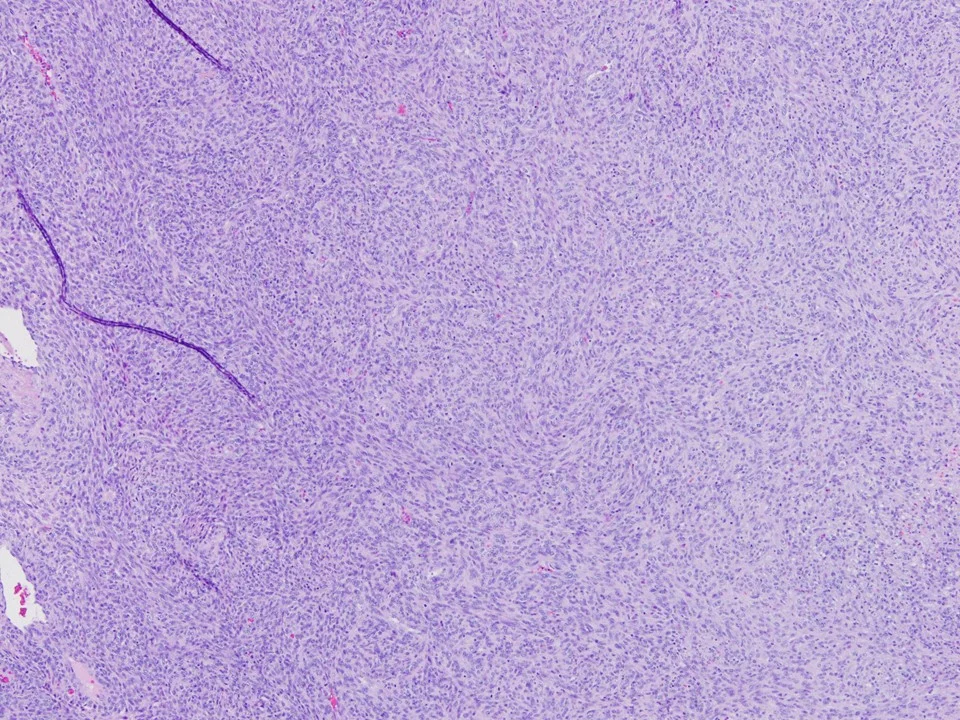

Invasive Lobular Carcinoma, Solid Variant

Variant forms of invasive lobular carcinoma differ from the classical form with regard to architectural and/or cytologic features. In the solid variant, the cells comprising the tumor are cytologically similar to those of the classical form of ILC. However, they differ with regard to growth pattern.

In the solid variant of invasive lobular carcinoma, the tumor cells grow in large confluent sheets with little intervening stroma.

The neoplastic cells of the solid variant of invasive lobular carcinoma show similar cytologic features to the classic type. The cells are small and uniform. Loss of cohesion, which is a feature commonly present in ILC, is demonstrated in this solid area.